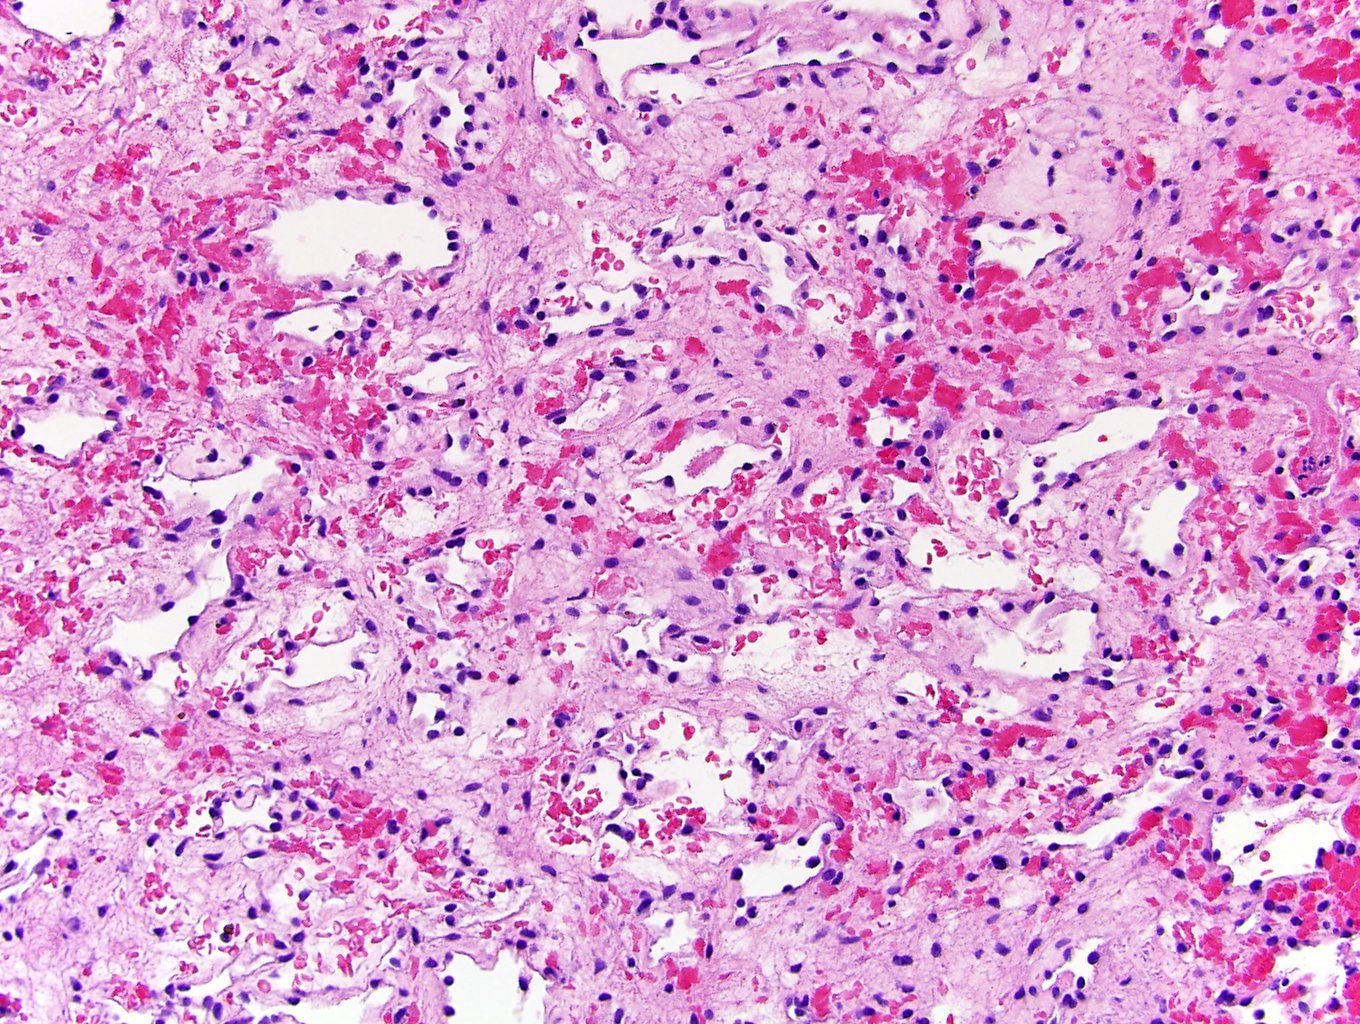

Microscopic (histologic) description

- Circumscribed, unencapsulated proliferation of irregular, blood filled vascular spaces lined by a single layer of endothelial cells

- Anastomosing hemangioma (AH):

- Capillary sized sinusoidal vessels with anastomotic arrangement

- Scattered hobnail endothelial cells

- Extramedullary hematopoiesis, fibrin thrombi, extensive perirenal fat entrapment, intravascular growth and mast cells may be seen (Histopathology 2014;65:309)

- Cytologic atypia and mitotic activity rare

- Regressive changes, including hyalinization, cystic changes and fatty overgrowth (Histopathology 2014;65:309)

Microscopic (histologic) images